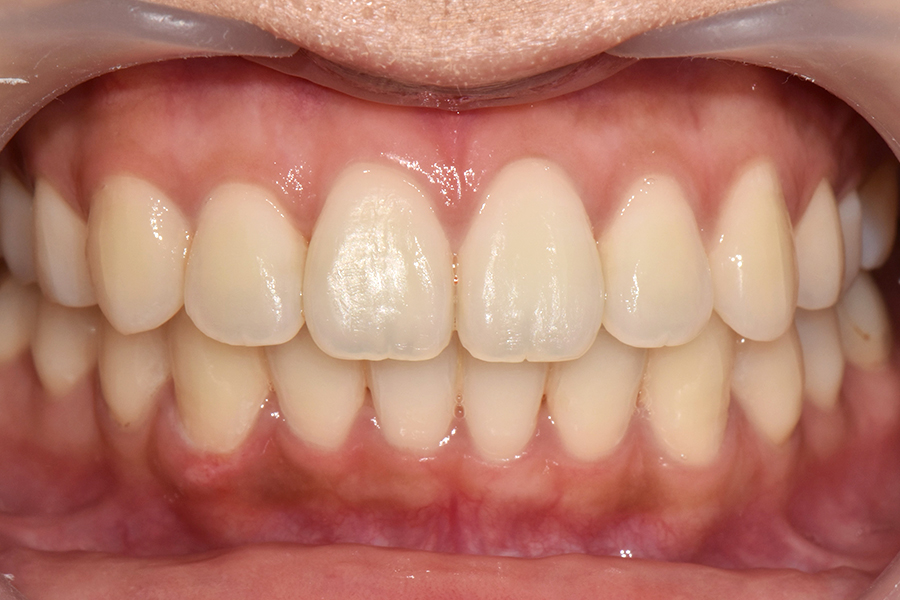

교정을 3월에 시작하셨는데 5개월이 지난 후의 모습입니다.

부분교정의 경우에는 중심선을 맞추기가 굉장히 어려운데 환자분 교합이 괜찮으시고 치아도 잘 움직여주셔서 가운데 선을 맞출 수 있게 되었고, 교합도 거의 전체교정을 한 것처럼 아주 예쁜 효과를 얻을 수 있었습니다.

때문에 환자분께서도 교정 결과에 굉장히 만족을 하셨고, 웃었을 때도 자연스럽게 치아 모양이 예쁘게 유지되는 것을 보실 수 있습니다.